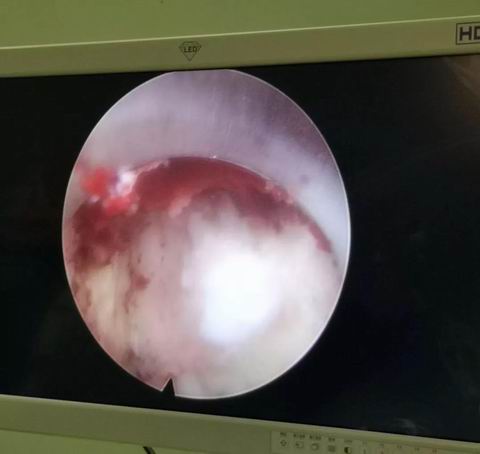

安钢总医院脊柱微创团队在通过仔细分析病人的临床资料与影像学特点后,并在患者拒绝开放手术的要求下,决定采用微创脊柱内镜下融合术preint-ELIF(Endoscopy Lumbar interbody fusion)。脊柱微创团队进行了精心地术前准备,于7月31日上午10点开始手术。手术中,王院长准确定位置管,经椎间孔镜下腰3/4椎间盘减压彻底,扩大手术通道至2厘米,通道下应用终板处理器处理终板,放置大小合适的融合器,最后结合经皮椎弓根螺钉复位脱位的腰4椎体并固定。此微创术式创伤小,术后恢复快,但手术难度大。

在经过整个脊柱微创团队3个小时的奋战后,手术圆满完成,出血量仅为传统手术的六分之一。目前,腰椎融合手术是治疗腰椎间盘疾患的主要方式,应用较多的仍是后路融合术(PLIF),这种手术虽然疗效确切、融合率较高,但需要在后背切开长约10cm的刀口,因为是直接减压,要破坏腰椎的肌肉、小关节、椎板等后柱结构,对脊柱后柱结构破坏较大,另外椎管内瘢痕增生易导致神经受压,故远期效果往往欠佳。微创脊柱内镜下融合术preint-ELIF(Endoscopy Lumbar interbody fusion),从侧路行椎间融合,不但植骨面积大,融合率高,还保留了后柱结构,避免了对椎管内结构的干扰。较传统ALIF及XLIF风险小,preint-ELIF技术简化了手术的过程,减少术中出血与组织创伤,减少术后疼痛与炎性反应导致的粘连,同时缩短住院时间并更有利于患者康复,是一项具有良好发展前景的技术,但此项技术难度较高并需要较长的学习曲线。